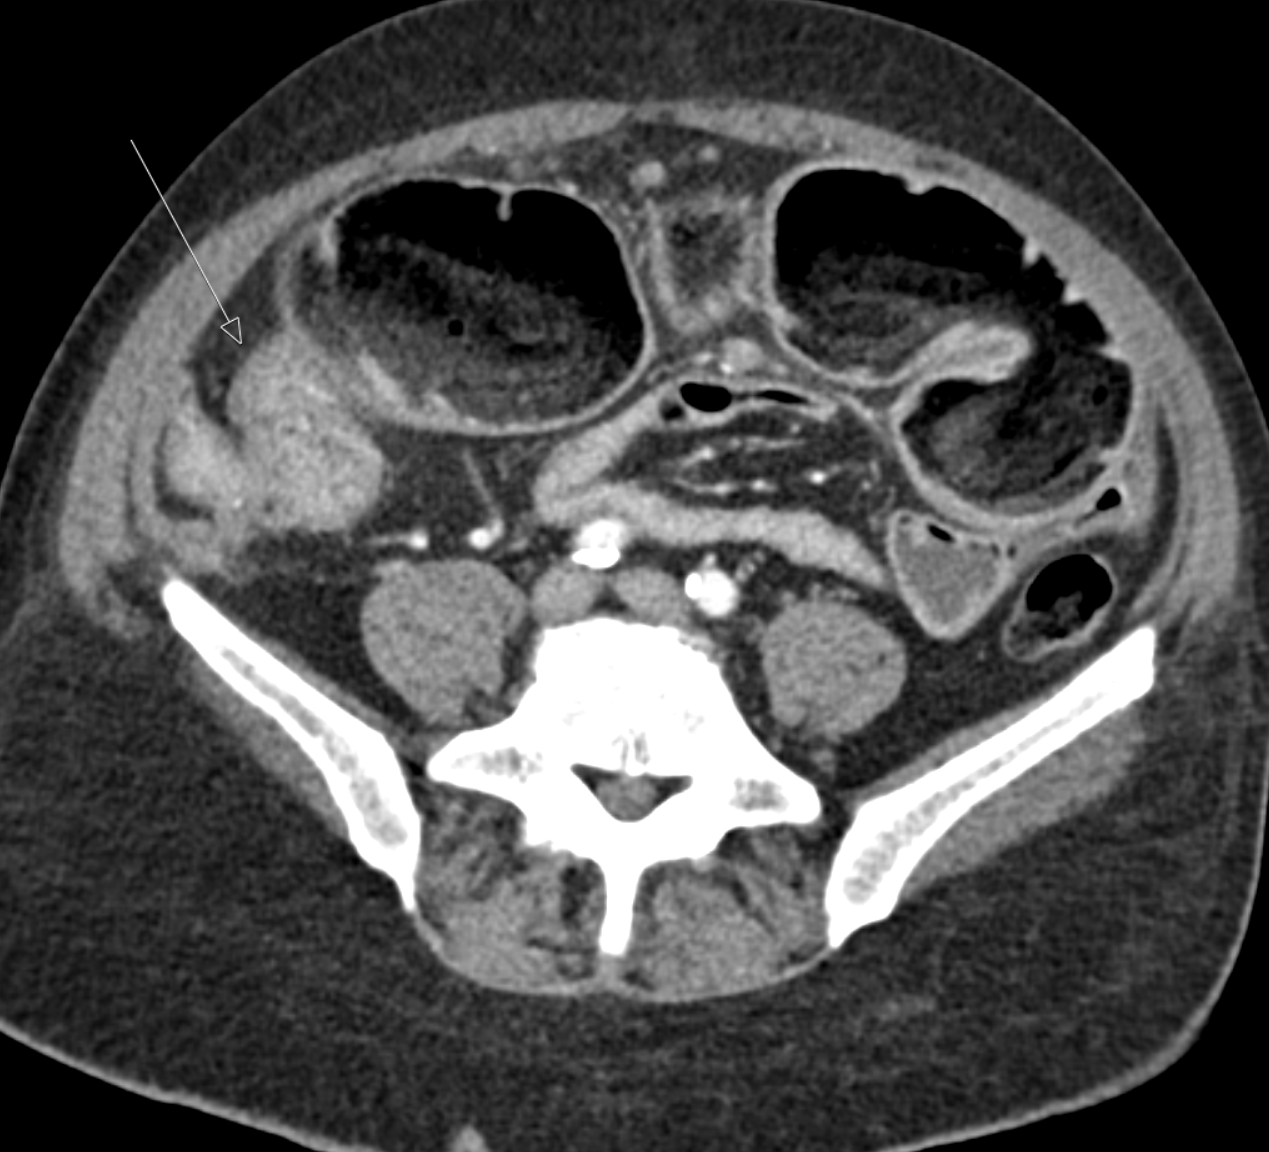

Case Presentation: A 61-year-old man with a history of GERD, tobacco, and alcohol use presented to our hospital with a week-long exacerbation of subacute abdominal pain and constipation. He had presented multiple times in recent months to outside hospitals with similar symptoms. CT and MRI scans showed a small bowel obstruction (SBO) with a transition point, terminal ileitis, and fat stranding. An EGD was unremarkable. Colonoscopy showed an ulcer of the ileocecal (IC) valve, a non-traversable stricture at the terminal ileum, and a 5 cm polyp in the descending colon. Biopsies showed normal ileal mucosa, focal acute colitis of the IC valve, and high-grade dysplasia of the polyp. GI and general surgery were consulted, a diagnosis of Crohn’s was made, his symptoms improved with steroids, and he was discharged on a prednisone taper with GI clinic follow-up. He was unable to present to the GI clinic due to recurrence of symptoms. When he presented to our hospital, the workup was remarkable for normal ESR, CRP, B12, CMP, and CBC. CT and MRI enterography with and without contrast showed findings similar to prior evaluations. GI recommended surgical resection for a stricture deemed unresponsive to medical management. In the operating room, an obstructing mass was noted at the IC valve. Pathology showed a 4 cm invasive poorly differentiated adenocarcinoma with metastases to multiple lymph nodes and the peritoneum.

Discussion: We present a case of SBO and stricture at the IC valve, suspected to be due to Crohn’s disease, but instead found to be an IC adenocarcinoma with peritoneal carcinomatosis. This case highlights the classic diagnostic complexity that internists face when there is significant overlap in the presentation between two diagnoses, and how early closure of the differential diagnosis can lead to missed opportunities to better care for our patients. The diagnosis of Crohn’s disease relies on a combination of symptoms, radiologic, endoscopic, and pathologic findings (1). While there is significant overlap between signs and symptoms in Crohn’s disease and cancer, several factors were concerning for cancer, including his age, smoking and alcohol history, absence of prior screening colonoscopies, and no family history of Crohn’s. He had a typical Crohn’s stricture and terminal ileal inflammation, but lacked features like bloody diarrhea, malabsorption, elevated ESR or CRP, or extraintestinal manifestations. Review of prior admissions revealed a CEA of 241; while CEA can be elevated in benign conditions, it rarely exceeds 30 in such cases (2). We highlight two important points: 1] Biopsy is critical in both Crohn’s and GI cancer, but colonoscopy was limited by an impassable stricture. In stricturing Crohn’s disease, European guidelines suggest early consideration of stricture resection, especially when dysplasia is found, due to the risk of undetected neoplasia in or proximal to the stricture (3). 2] CT and MR enterography have sensitivities of 75.9% and 92.6% for small bowel neoplasms, respectively. Cancerous lesions may be missed due to overlap with benign strictures (e.g., mild or symmetric wall thickening) or loss of mural stratification from chronic inflammation or fibrosis; thus, special care needs to be taken to not rule out cancer based on prior imaging (4-6).